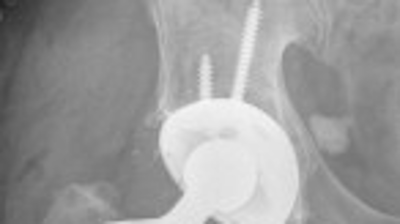

5 Things You Didn’t Know About Depuy Hip and Knee Replacements